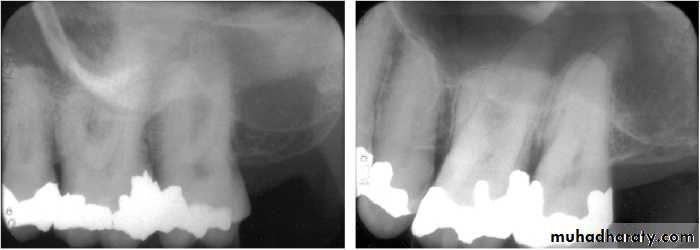

Gutta Percha POINT TRACING

Can localize the endodontic lesion to the specific tooth.Aids in the differential diagnosis between a periodontal and an endodontic lesion.

Placing a gutta percha point through the sinus/fistula tract and take a radiograph.